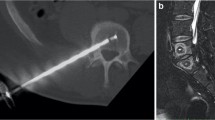

Study interventions

The BVN ablation was performed under image guidance in an outpatient setting using the Intracept ® System (Relievant Medsystems, Minneapolis, MN, USA). The target zone for BVN ablation is midline in the posterior aspect of the vertebral body, typically between 31 and 50% from the posterior to anterior of the vertebral body. Mean operative times of 60–90 min were recorded. Detailed information about the surgical technique was previously described [13]. No additional interventions were required in the five plus year follow-up study.

Target success